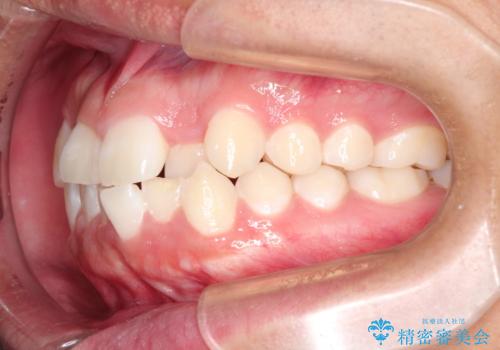

- 前歯のがたつきを主訴に来院されました。

上顎の前から2番目の歯の噛み合わせが反対になっていました。

抜歯矯正も考えられるケースでしたが、非抜歯での矯正を希望され、インビザラインにて治療することとなりました。

目立たずに矯正を終えることができ、患者様にも満足していただきました。